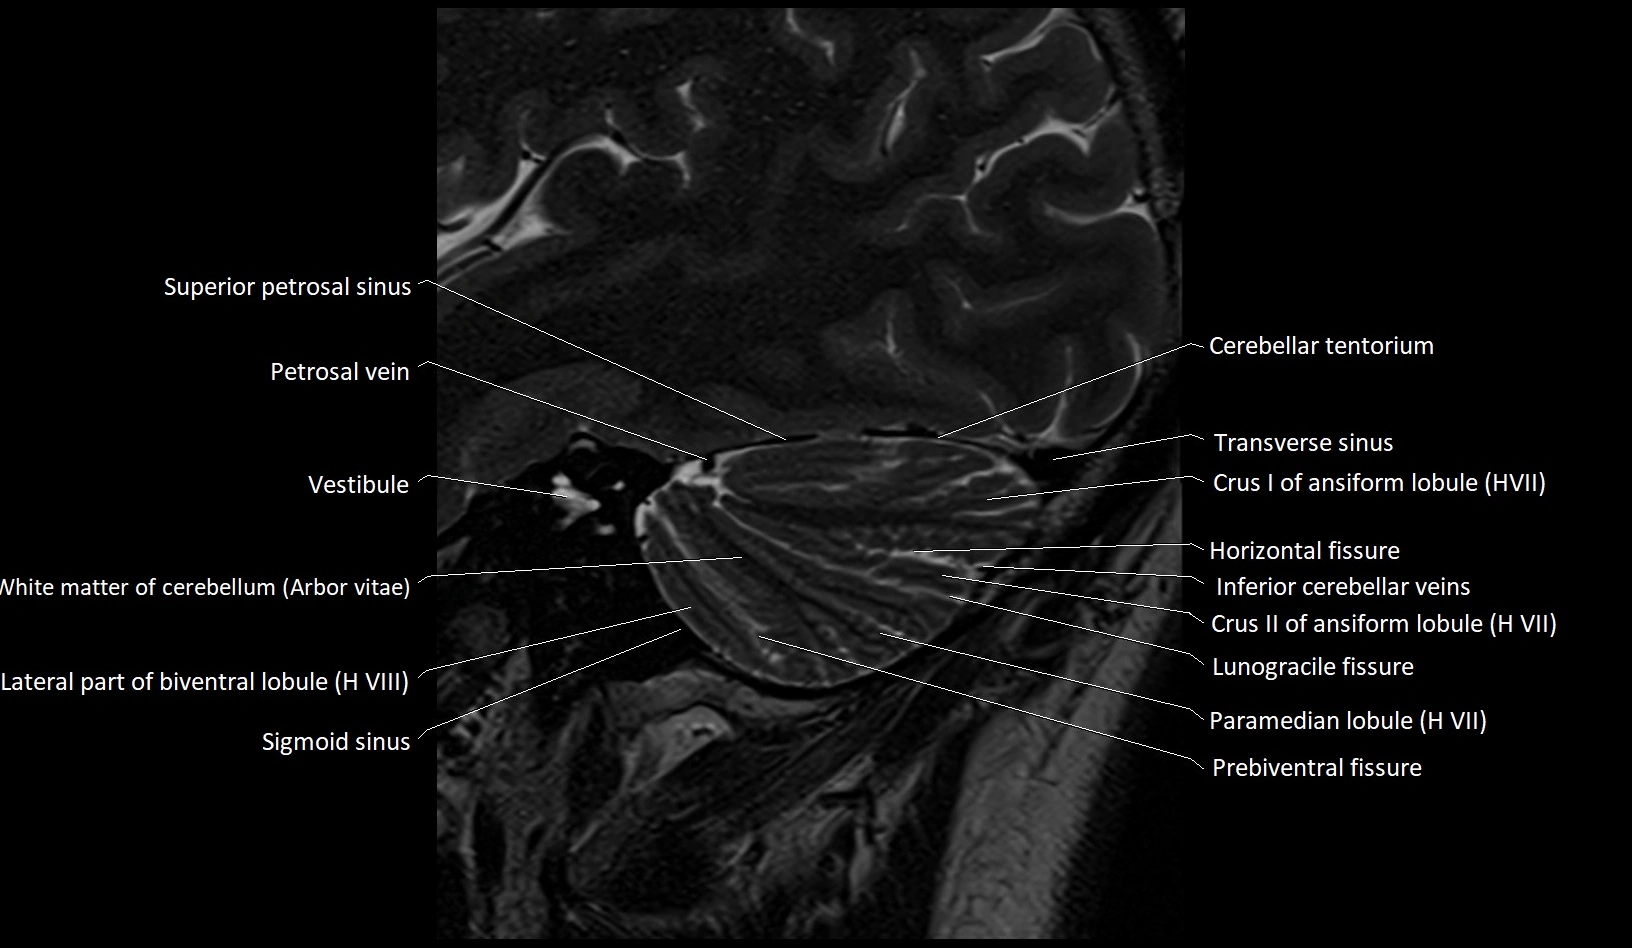

MRI images